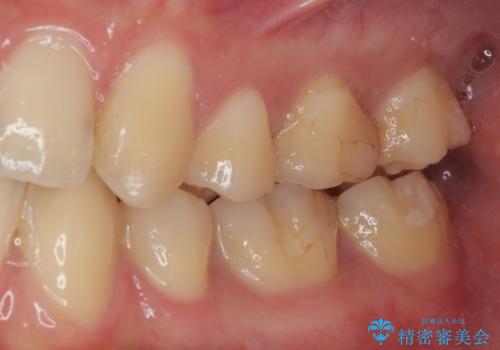

虫歯による不快な症状がなくなり喜んでいただきました。セラミックの被せものが入った後の違和感なく過ごせているそうです。矯正治療終了直後の被せもの治療なのでリテーナーの作成回数をできるだけ少なく迅速に行うことを考慮して治療を行いました。

今後、ホワイトニングを行う予定なので、患者様のご希望により、周りの歯に比べてあえて白い被せものを作成しました。